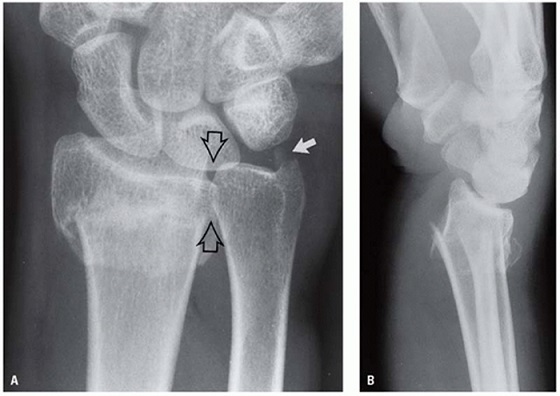

1-4: تشخیص شکستگی انتهای ساعد: تشخیص قطعی این شکستگی با رادیوگرافی ساده است. در رادیوگرافی ساده خط شکستگی بالای سطح مفصل مچ دست دیده میشود. قطعه بین خط شکستگی و مفصل مچ دست به سمت پشت و خارج جابجا میشود. گاهی این قطعه شکسته شده خرد بوده و گاهی خط شکستگی به درون مفصل مچ هم راه پیدا میکند .